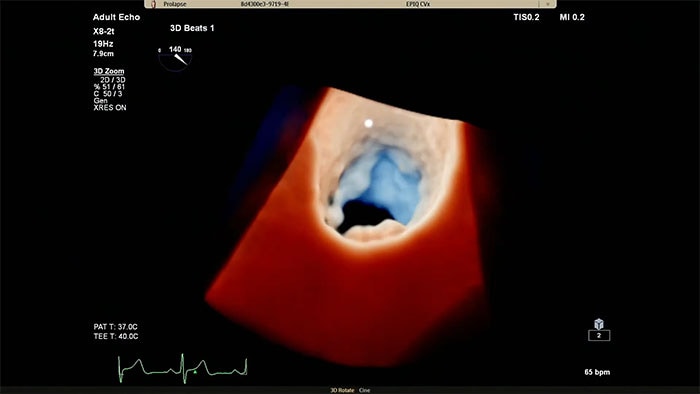

View enhanced visualizations of structures and flow with TrueVue Color

Visualize cardiac morphology using ultrasound with TrueVue Glass